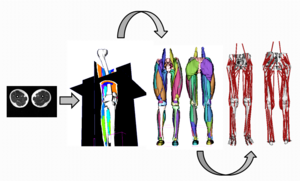

- 7.17 Subject-specific Musculoskeletal Modeling of the Lower Extremities in Persons with Unilateral Cerebral Palsy